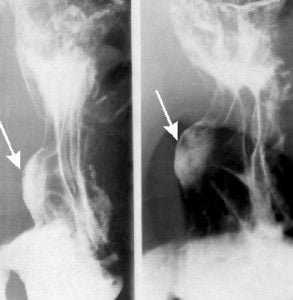

• ULCUS CURVATURA MENOR. ESPASMO EN LA MAYOR